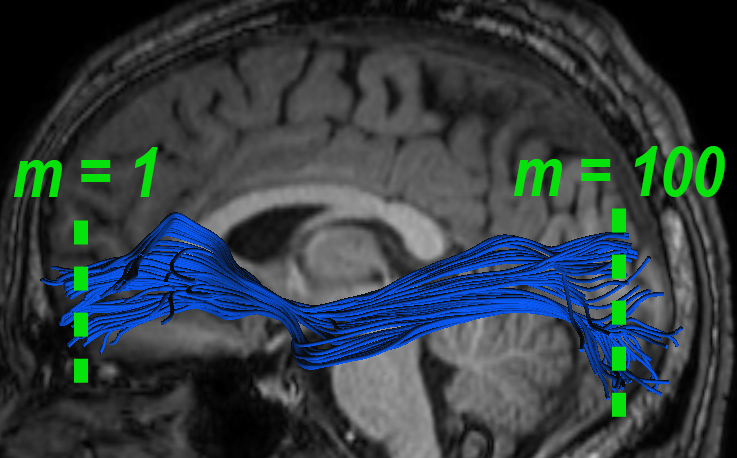

where is a scalar used for regularization, set as in [10]. Given , the FMM solves the Eikonal equation providing as output the weighted distance matrix Fig.1a-b present and , respectively. The optimal alignment is then defined by the shortest path in from the starting point to the endpoint . The alignment path defines pairs of matching points between the bundles, and is computed with sub-voxel resolution as follows:

| (4) |

as illustrated in Fig. 1c. The step size is usually set to some small value ( For uniformity, we re-sample into samples, i.e., , such that the aligned mean fibers are obtained by and (see Fig. 1d), and their tract-profiles are aligned accordingly: and .